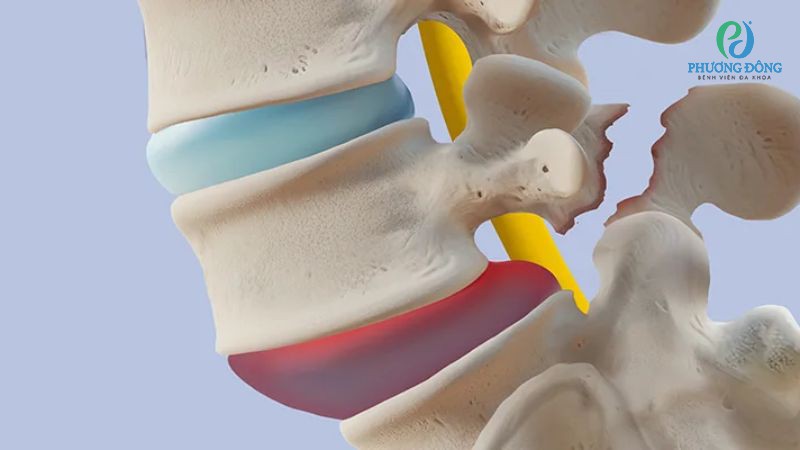

Trượt đốt sống xảy ra khi một trong các đốt xương cột sống bị trượt khỏi vị trí thông thường, chèn ép lên đốt sống phía dưới. Tình trạng này có thể gây áp lực lên các dây thần kinh xung quanh, khởi phát cơn đau lưng kèm theo các triệu chứng khác.

Trượt đốt sống là tình trạng đốt xương cột sống bị trượt khỏi vị trí giải phẫu

Do thoái hóa

Thoái hóa là nguyên nhân gây bệnh thường gặp nhất, cơ thể lão hóa khiến các đĩa đệm nằm giữa đốt sống bị bào mòn và mất đi khả năng đàn hồi. Đĩa đệm mỏng đi làm thay đổi khoảng cách giữa các đốt sống, tăng nguy cơ trượt khỏi vị trí ban đầu.

Thoái hoá là một trong những nguyên nhân gây trượt đốt sống